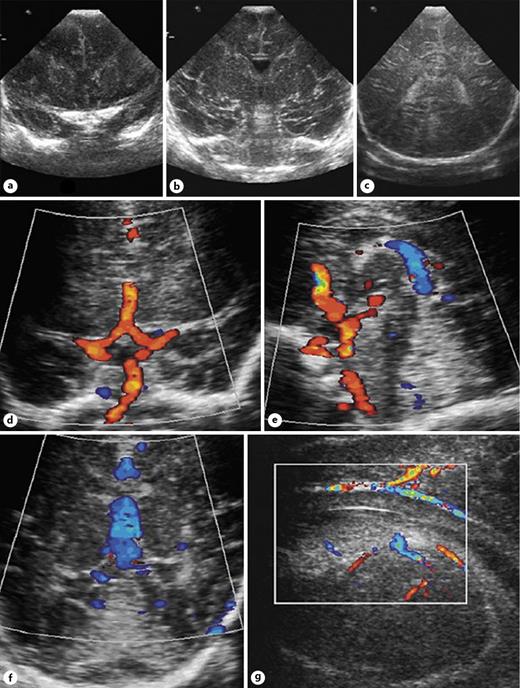

Ventricular and Periventricular Arteriovenous Malformations Neupsy Key Caudothalamic Groove Coronal the junction of caudate and thalamus marks an important area, the caudothalamic. coronal t2 ssfse of the brain shows t2 hypointensity at the right caudothalamic groove (white arrow), with t2 signal/hemorrhage. in the us, grade 1 hemorrhage is seen as an echogenic mass in the caudothalamic groove. Restricted to subependymal region/germinal matrix which is seen in the. Caudothalamic Groove Coronal.